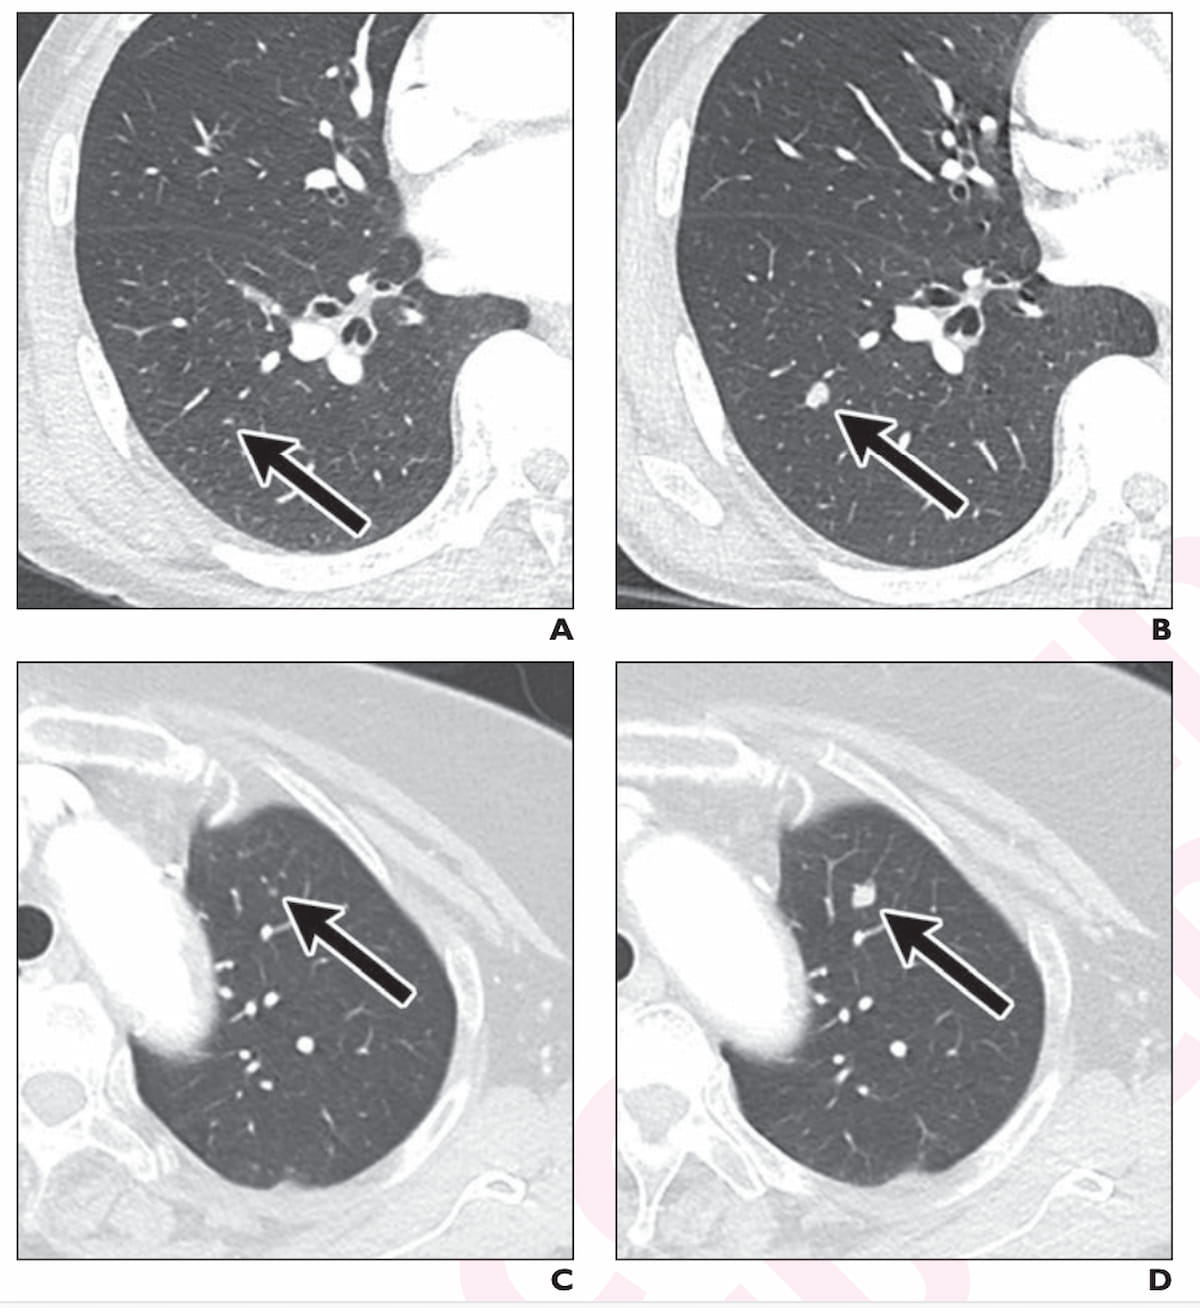

Here one can see axial CT images for two false-negative cases revealing lung nodule growth that was subsequently confirmed as metastasis for a 71-year-old man with stage 3 rectal cancer (A and B) and an 81-year-old woman with stage 3 ascending colon cancer (C and D). (Images courtesy of the American Journal of Roentgenology.)

In cases involving missed metastases, the researchers noted a smaller missed nodule size with adjunctive AI interpretation (mean of 3.1 mm) in comparison to unassisted radiologist interpretation (mean of 4.7 mm).